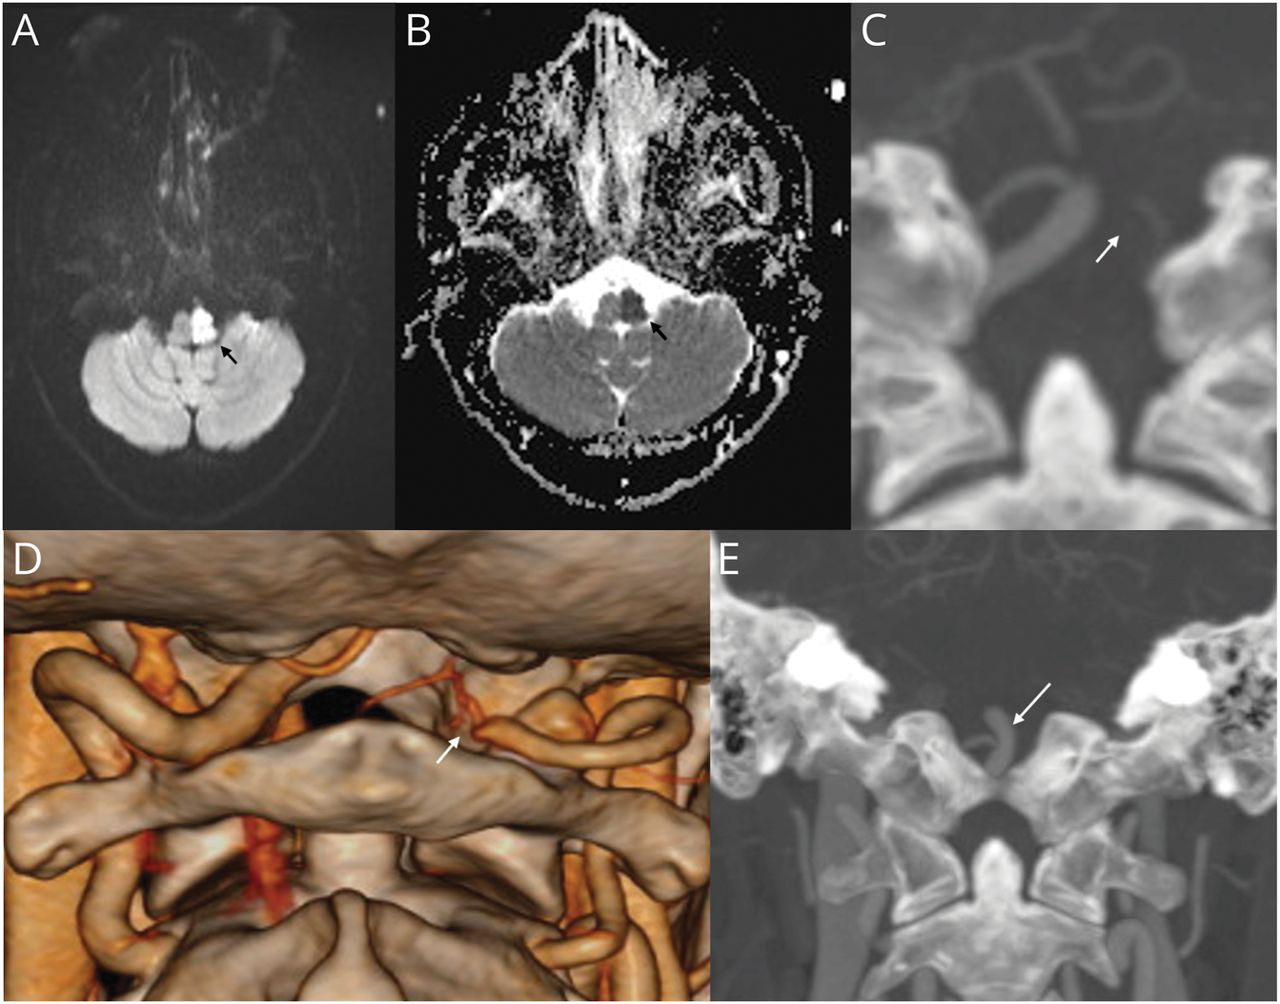

脑非对比MRI显示扩散加权成像显示高信号累及左半脑(A;黑色箭头),在表观扩散系数序列(B;黑色箭头),提示急性梗死。冠状位CT脑血管造影显示左椎动脉V4段未显示(C;白色箭头)和完整的基底动脉远端血流(E;白色箭头)。三维阴影表面显示体绘制(SS-VRT)重建图像显示左椎动脉V4段突然闭塞(D;白色箭头)。

32岁男性,无血管危险因素,急性起病眩晕,吞咽功能障碍,右侧无力。体格检查显示左侧有以下体征:霍纳综合征;下运动神经元第9、10、12脑神经麻痹;小脑肢体共济失调;面部疼痛和体温下降;面部,躯干和四肢的精细触觉和本体感觉丧失。在右侧,他有偏瘫,躯干和四肢疼痛和体温下降。脑核磁共振显示急性脑梗塞累及髓质左半部(图,A和B).头颈部血管CT造影显示左椎动脉V4段闭塞(图C, D, E).诊断为Reinhold完全性半髓质综合征(表格).1,-,3.几乎类似的Babinski-Nageotte不完全半髓样综合征缺乏同侧舌下神经麻痹。2中风病因检查显示正常的糖化血红蛋白,血脂,阴性的高凝,自身免疫和血管炎组。超声心动图正常,长时间心脏遥测未见心律失常。他维持乙酰水杨酸100 mg,每日1次,夜间阿托伐他汀40 mg,用于二次卒中预防。